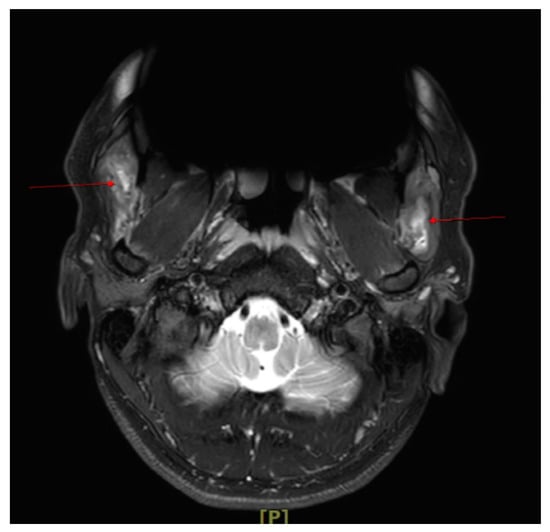

2.1.2. Imaging

2.2.2. Imaging